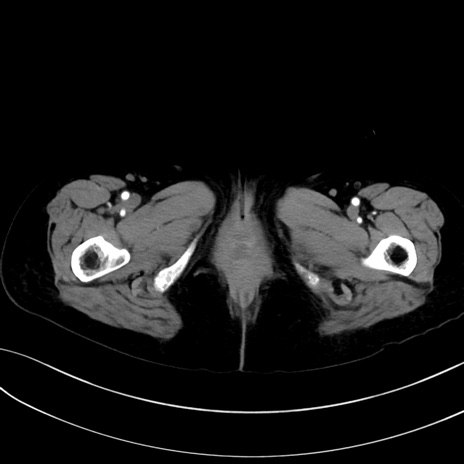

(冠状断像)1日半後